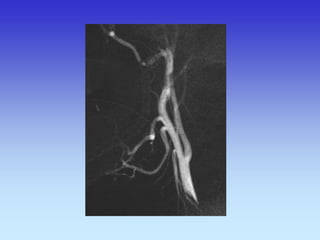

METODE PRIKAZA KRVNIH ŽILA

•UZ-DOPPLER

•DSA

•CTA

•MRA